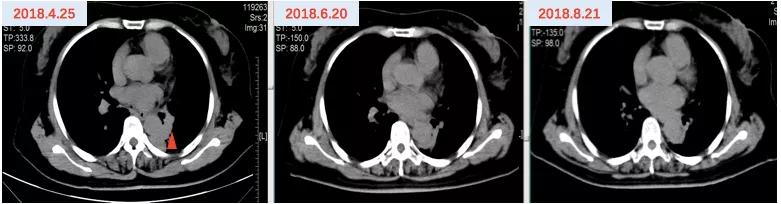

2019年2月26日因“活动后气促”于福建省东山县医院查胸部CTA示:左肺癌及化疗后改变,双肺下叶少许炎性灶,纵隔内及双肺门淋巴结肿大,肝内低密度灶,考虑转移灶?左右肺动脉局部及其部分分支充盈缺损,考虑癌栓形成。分子病理(ctDNA,ddPCR)EGFR T790M 0.89%。2019年2月28日开始口服“奥希替尼80mg qd”靶向治疗,并予低分子肝素抗凝治疗。2019年3月26日复查提示肺动脉瘤栓较前好转,左肺病灶较前略增大。(图6)

因考虑左肺病灶较前略增大,患者继续口服“奥希替尼80mg qd”靶向治疗,并于2019年3月26日开始联合“长春瑞滨40mg d1,3,5(口服3周停1周)”节拍化疗,定期复查疗效评价SD,PFS接近12个月。(图7)

图6 奥希替尼治疗前后影像资料

图7 “奥希替尼+长春瑞滨”治疗前后影像资料